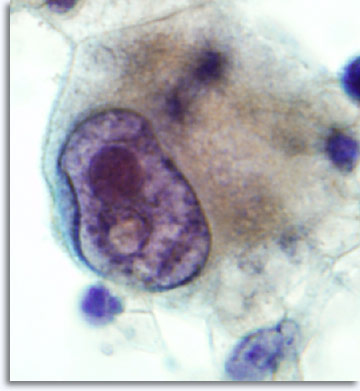

Als patroonherkenning niet onmiddellijk resulteert in een specifieke diagnose en categorie-indeling, kunnen aanvullende technieken zoals immuuncytochemie moleculaire informatie leveren die een bijdrage zal leveren voor de classificatie. Bij infectueuze processen is het mogelijk om specifieke etiologische infectie-agentia te isoleren, aantoonbaar met de Papanicolaou kleuring, Giemsma kleuringen voor bacteriën, en AFB kleuringen voor zuurvaste bacillen en PAS en GMS voor fungale organismen.

|

De monsterpresentatie kan licht variëren, afhankelijk van het feit of de cellen rechtstreeks op objectglaasjes zijn geplaatst of dat ze verwerkt zijn via vloeibare ThinPrep® technologie. De directe uitstrijkjes zullen achtergrondmateriaal en bloed bevatten, kernen van maligne cellen zullen gewoonlijk hyperchromatischer lijken en dens. Met ThinPrep wordt de cellulaire aggregatie gehandhaafd, terwijl achtergrondbloed wordt gelyseerd en kernen van maligne cellen minder dens en hyperchromatisch lijken. Een uitzondering kan voorkomen met de matglas vesiculatie die kenmerkend is voor papillair schildkliercarcinoom, waarin de optische veranderingen van de kernen gelijk zijn in zowel conventionele en op vloeistof gebaseerde presentaties.